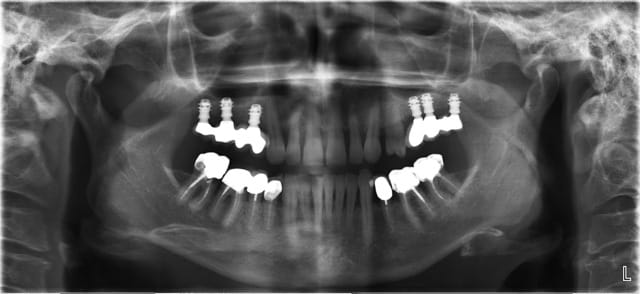

Bonjour j'ai un cas où le 6 mm s'impose (systeme alphabio) est ce que certains de vous l'ont utilisé

une petite pano pour qu'on se rende compte?

Pour Pluton

voici le cas extraction en décembre 2011 ce qui me pose problème c'est le 2eme implant le 8 mm passe mais le col ne serait pas enfoui , ne vaut il donc pas mieux plus enfouir un 6 mm d'où ma question.

L'os dans le 2 eme site est type 4 et type 3 vers le fond et avec le 8 mm je me retrouve dans la corticale linguale

une petite pano pour une vue d'ensemble?

parce que j'ai l'impression qu'il y a une concavité...donc çà peut être l'indication d'implants pas totalement enfouis + rog pour retrouver une crête sympa...

sinon le deuxième site, moi, me paraît louche...c'est pas du D4, j'aurais plutôt tendance à dire que c'est du tissu de granulation...( et peut être bien un petit morceau de racine...c'est pas très net...)